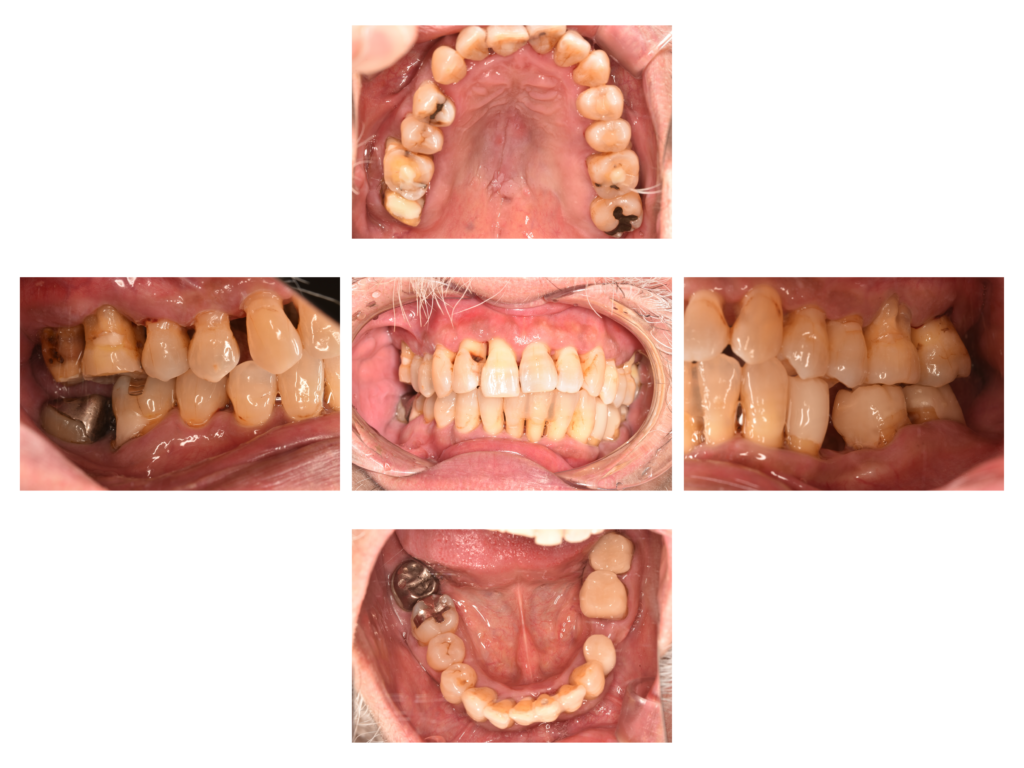

患者さんは下の前歯が揺れることを主訴に来院されました。家族から口臭も指摘されていたそうです。

歯磨きはしっかりされているそうですが、歯肉付近のブラッシングが不十分で歯石が多くの部位に沈着していました。

歯間ブラシから治療を始めています。ひたすら歯間ブラシの指導とSRPをおこなっています。

重度歯周病の部位が多数あり、歯周病により根管治療(神経の治療)が必要な歯も複数あったので、その治療も同時におこなっています。

↑現在は歯磨きの状態が改善し、綺麗で引き締まったピンクの歯肉が維持されています。顕著な歯肉の退縮を全体的に認めますが、このまま経過を見続けます。今でこの歯肉退縮ですから、臼歯(奥歯)の歯周外科治療をするともっと歯肉が下がってしまいます。

歯肉が引き締まったことで全体的に知覚過敏が生じるようになっています。歯周病治療後は治療前に比べて歯根露出が目立ってしまいます。露出部分は象牙質でありムシ歯リスクが高いです。今後はムシ歯(根面う蝕)のチェックも欠かせません。